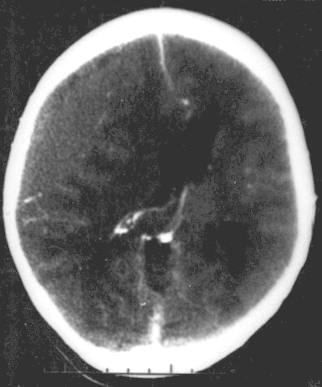

Epidural Hematoma

An epidural hematoma develops when blood accumulates between the skull and dura mater.

Epidural hematomas are usually the result of skull fracture and rupture of a major vessel of the brain.

Radiology of epidural hematomas classically show a lens-shaped lesion representing the dura separated from the skull by hemorrhage.